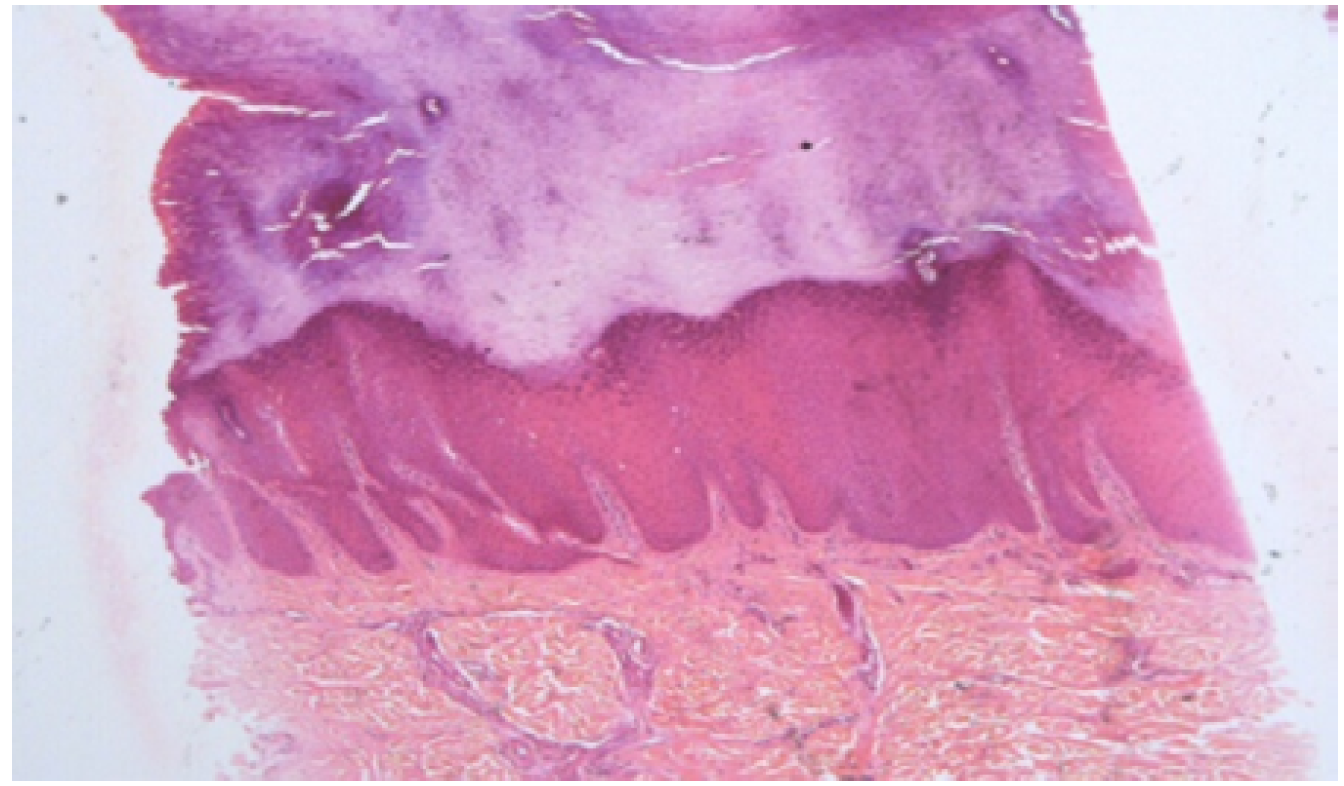

Oral mucosa, teeth and nails were not involved in both the mother and daughter. Histopathological examination of the biopsy taken from the sole of the patient revealed massive orthokeratotic hyperkeratosis, hypergranulosis and acanthosis without epidermolysis which was consistent with Unna-Thost disease (Figure 2).

Figure 2: Histopathological Examination of the Biopsy Taken from the Sole of the Patient Revealed Massive Orthokeratotic Hyperkeratosis, Hypergranulosis and Acanthosis without Epidermolysis which was Consistent with Unna-Thost Disease